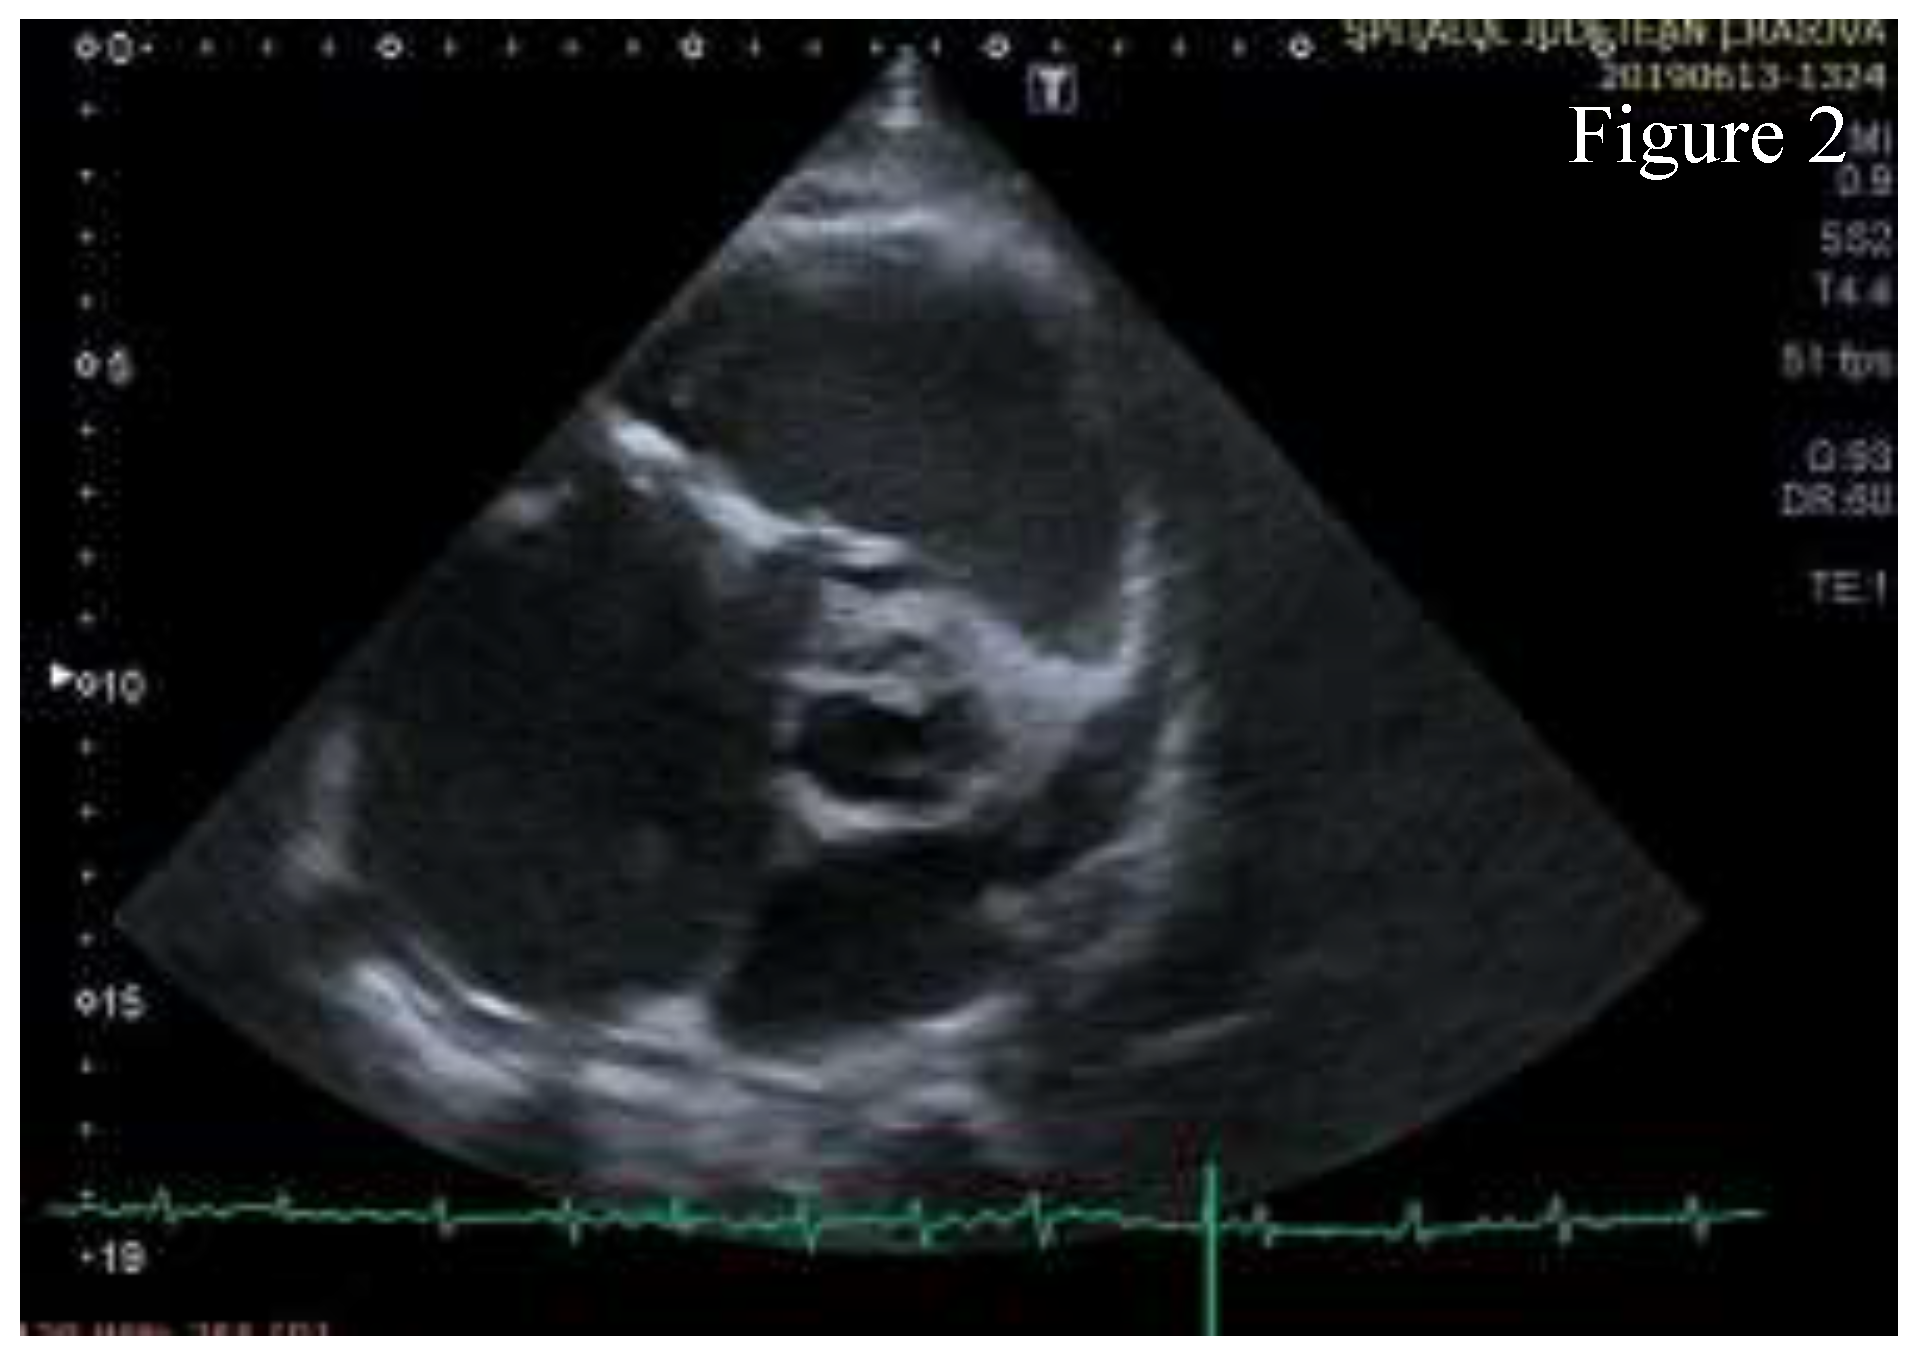

Transthoracic echocardiography (TTE) showed significant structural changes in the tricuspid valve. Anterior and posterior cusps were thickened, calcified, and had restricted motion. Subvalvular chords were thickened. Structural changes caused severe regurgitation (effective regurgitant orifice area= 0.57 cm2, regurgitant volume= 45 ml) and moderate stenosis (high diastolic gradient of 13/6 mmHg which contributed to the high inflow accompanying severe regurgitation). Right chambers were dilated with right ventricle longitudinal systolic dysfunction (TAPSE= 16mm, S’value = 10 cm/s) and with dilated inferior vena cava indicating increased pressure in the right atrium. These aspects are shown in Figure 1, Figure 2, Figure 3, Figure 4, Figure 5.

Figure 2.

Parasternal short axis view- the anterior cusp of the tricuspid valve is thickened and calcified, chordae tendinae are thickened, right atrium is dilated and a calcification area is found on the aortic right coronary cusp.